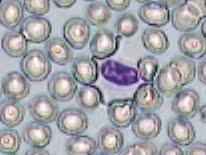

Imágenes tomadas de las preparaciones de los alumnos de 3º ESO sobre un frotis sanguíneo